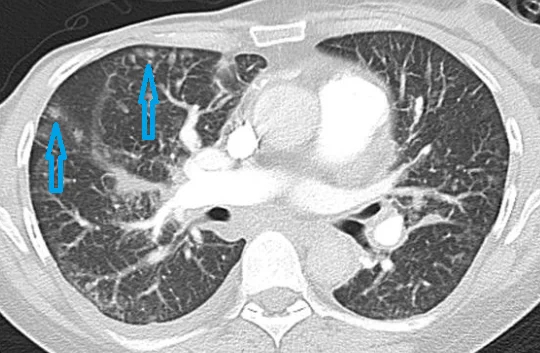

Размер – от милиарных (в переводе с латинского milium – просяное зернышко, то есть очаги совсем мелкие) до крупных. Причем хоть понятие «милиарные очаги» у людей, так или иначе связанных с медициной, ассоциируется с одноименной формой туберкулеза, при которой в обоих легких обнаруживаются многочисленные мелкие очаги, это не единственное заболевание с такой картиной, а лишь отражение ситуации, что очаги распределились по всем легким и, скорее всего, из кровеносных сосудов с частичками содержимого крови, то есть носят гематогенный характер. И нередко это содержимое - инфекционный или другой воспалительный агент, но также может оказаться и метастазами опухолей. Наличие картины множественных милиарных очагов (или, по-другому, диссеминация) требует дообследования.

2.Количество – одиночные (солитарные), немногочисленные или множественные.

3. Локализация – где расположены, от одного сегмента одного легкого до всех долей обоих легких.

- центрилобулярные - внутри мельчайших легочных структур – вторичных легочных долек (список болезней, проявляющихся такими очагами огромен, от бронхиолита – воспаления бронхиол - структур, которые меньше бронхов, до интерстициальных заболевания – группы болезней, так скажем, самого легочного каркаса);

- перилимфатические - вдоль лимфатических сосудов и плевры, так как по ней также проходят такие сосуды (к такому расположению, например, тяготеют очаги саркоидоза, представляющие сомой гранулемы или, что более грозно, лимфогенный карциноматоз – распространение опухолевых клеток);

- хаотичные – расположенные без четкой привязанности (так часто ведут себя упомянутые в разделе про размер очаги гематогенного распространения).